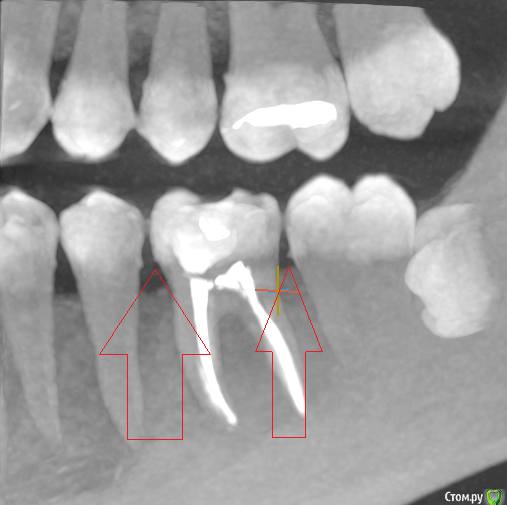

Доброго. Речь скорее всего о 36 зубе. У Вас имеются зубные отложения (камни см.рис.) которые так же могут поддерживать воспалительный процесс влияющий на возникновение болей в зубе при надавливании. Также необходимо дифференцировать нет ли болевого синдрома из-за 38 зуба ( неправильное положение с упором в 37 ). Если даже все вышеперечисленное не является причиной болей , то может болеть зуб , иногда бывают ответвления в сторону от канала ближе к верхушке корня , которые пройти ( пролечить) крайне затруднительно , или не представляется возможным физически ....исключите сначала 2 первых пункта.